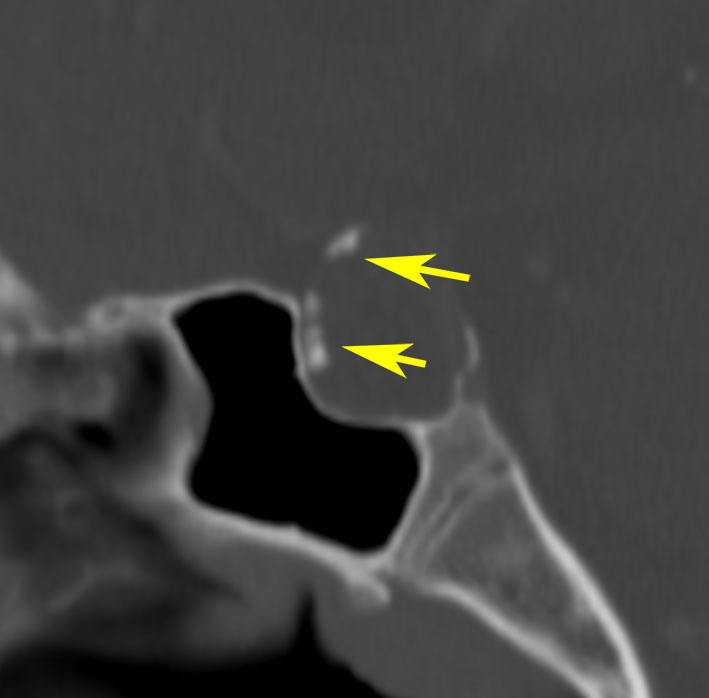

7歳の子が視力障害で発症しました。両耳側半盲という症状です。典型的な鞍隔膜下頭蓋咽頭腫です。ガドリニウム造影剤を入れないMRIでみえる,黄色い矢印の先の白い高信号は抗利尿ホルモンです。ですから下垂体機能もまだ残っていて,尿崩症はありません。視力障害が戻らないことがあるのでなるべく早く,経鼻的な手術で摘出した方がいいものです,簡単 o(^-^)o